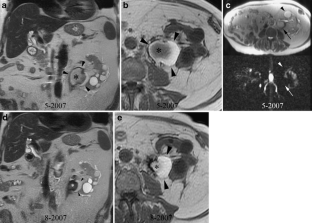

Fig. 2